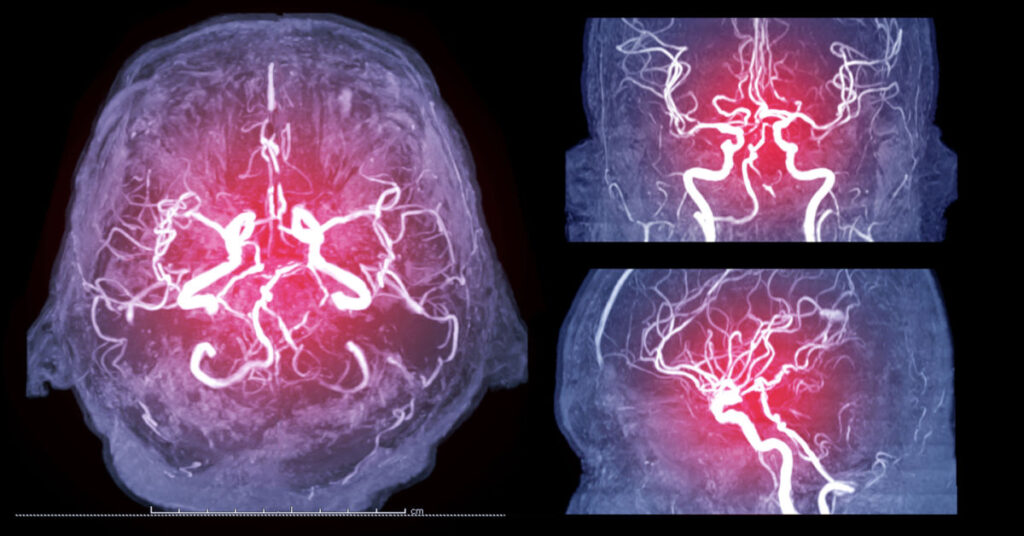

Що таке церебральна ангіографія

Церебральна ангіографія – це процедура, яка дає змогу перевірити наявність аномалій, звужень та бляшок у кровоносних судинах головного мозку методом рентгенологічного дослідження судин головного мозку та шиї.

- результати церебральної ангіографії чіткіші, ніж результати ультразвукової доплерографії сонних артерій або іншої неінвазивної візуалізації кровоносних судин;